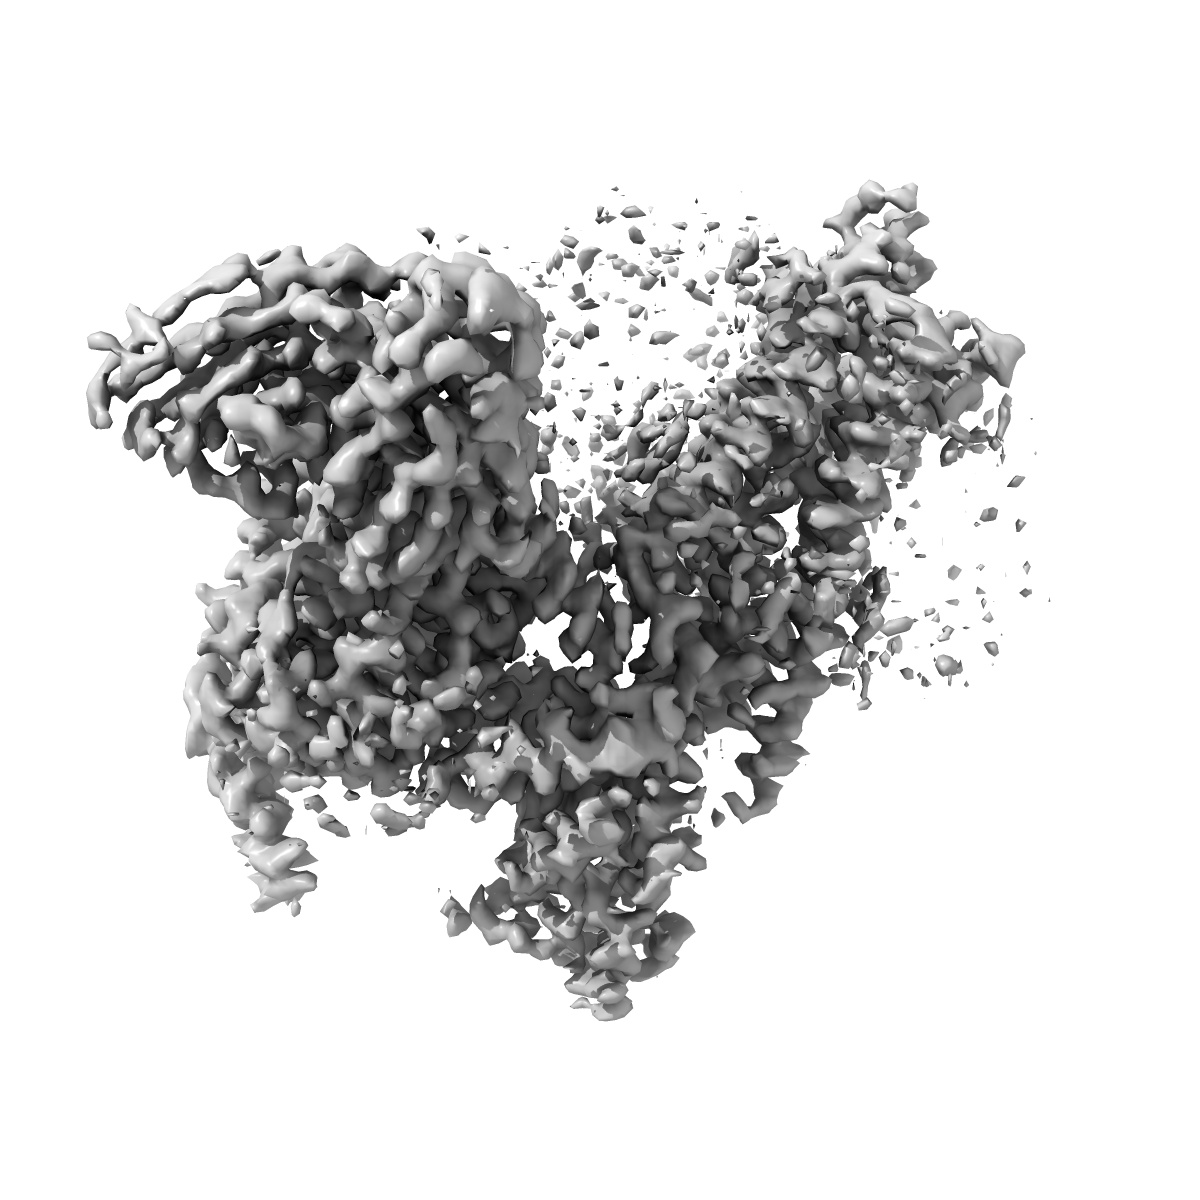

human Neurotensin Receptor 1 (hNTSR1) - Gi1 Protein Complex in canonical conformation (C state)

Single-particle3.0 Å

Sample: hNTSR1-Gi1 complex in canonical conformation (C state)

Conformational transitions of a neurotensin receptor 1-Gi1complex.